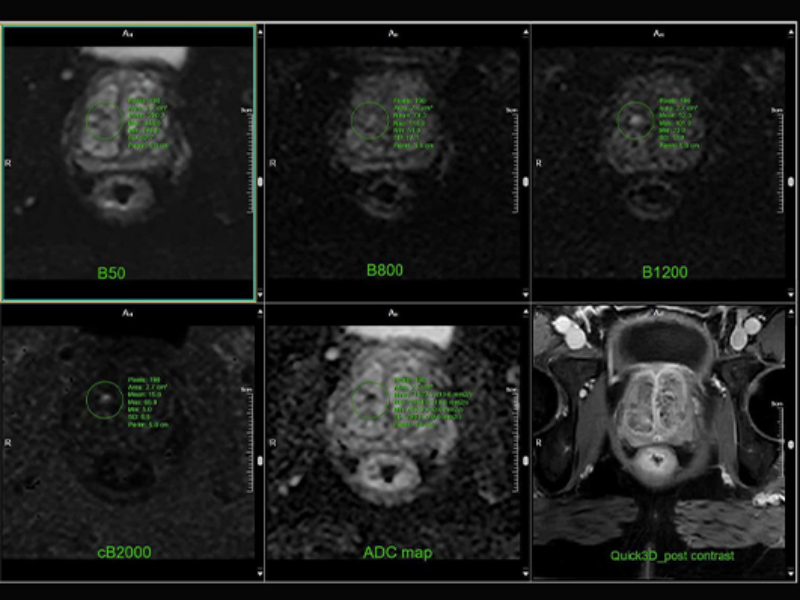

Prostate- DWI with post QUICK 3D